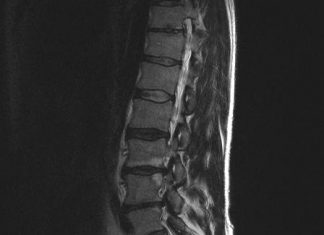

Nieuwe herniabehandeling (PTED) voorlopig vergoed

De afkorting staat voor Percutaan Transforminale Endoscopische Descectonomie. Dat betekent dat de zwelling van de hernia wordt verwijderd via je een klein sneetjeaan de...